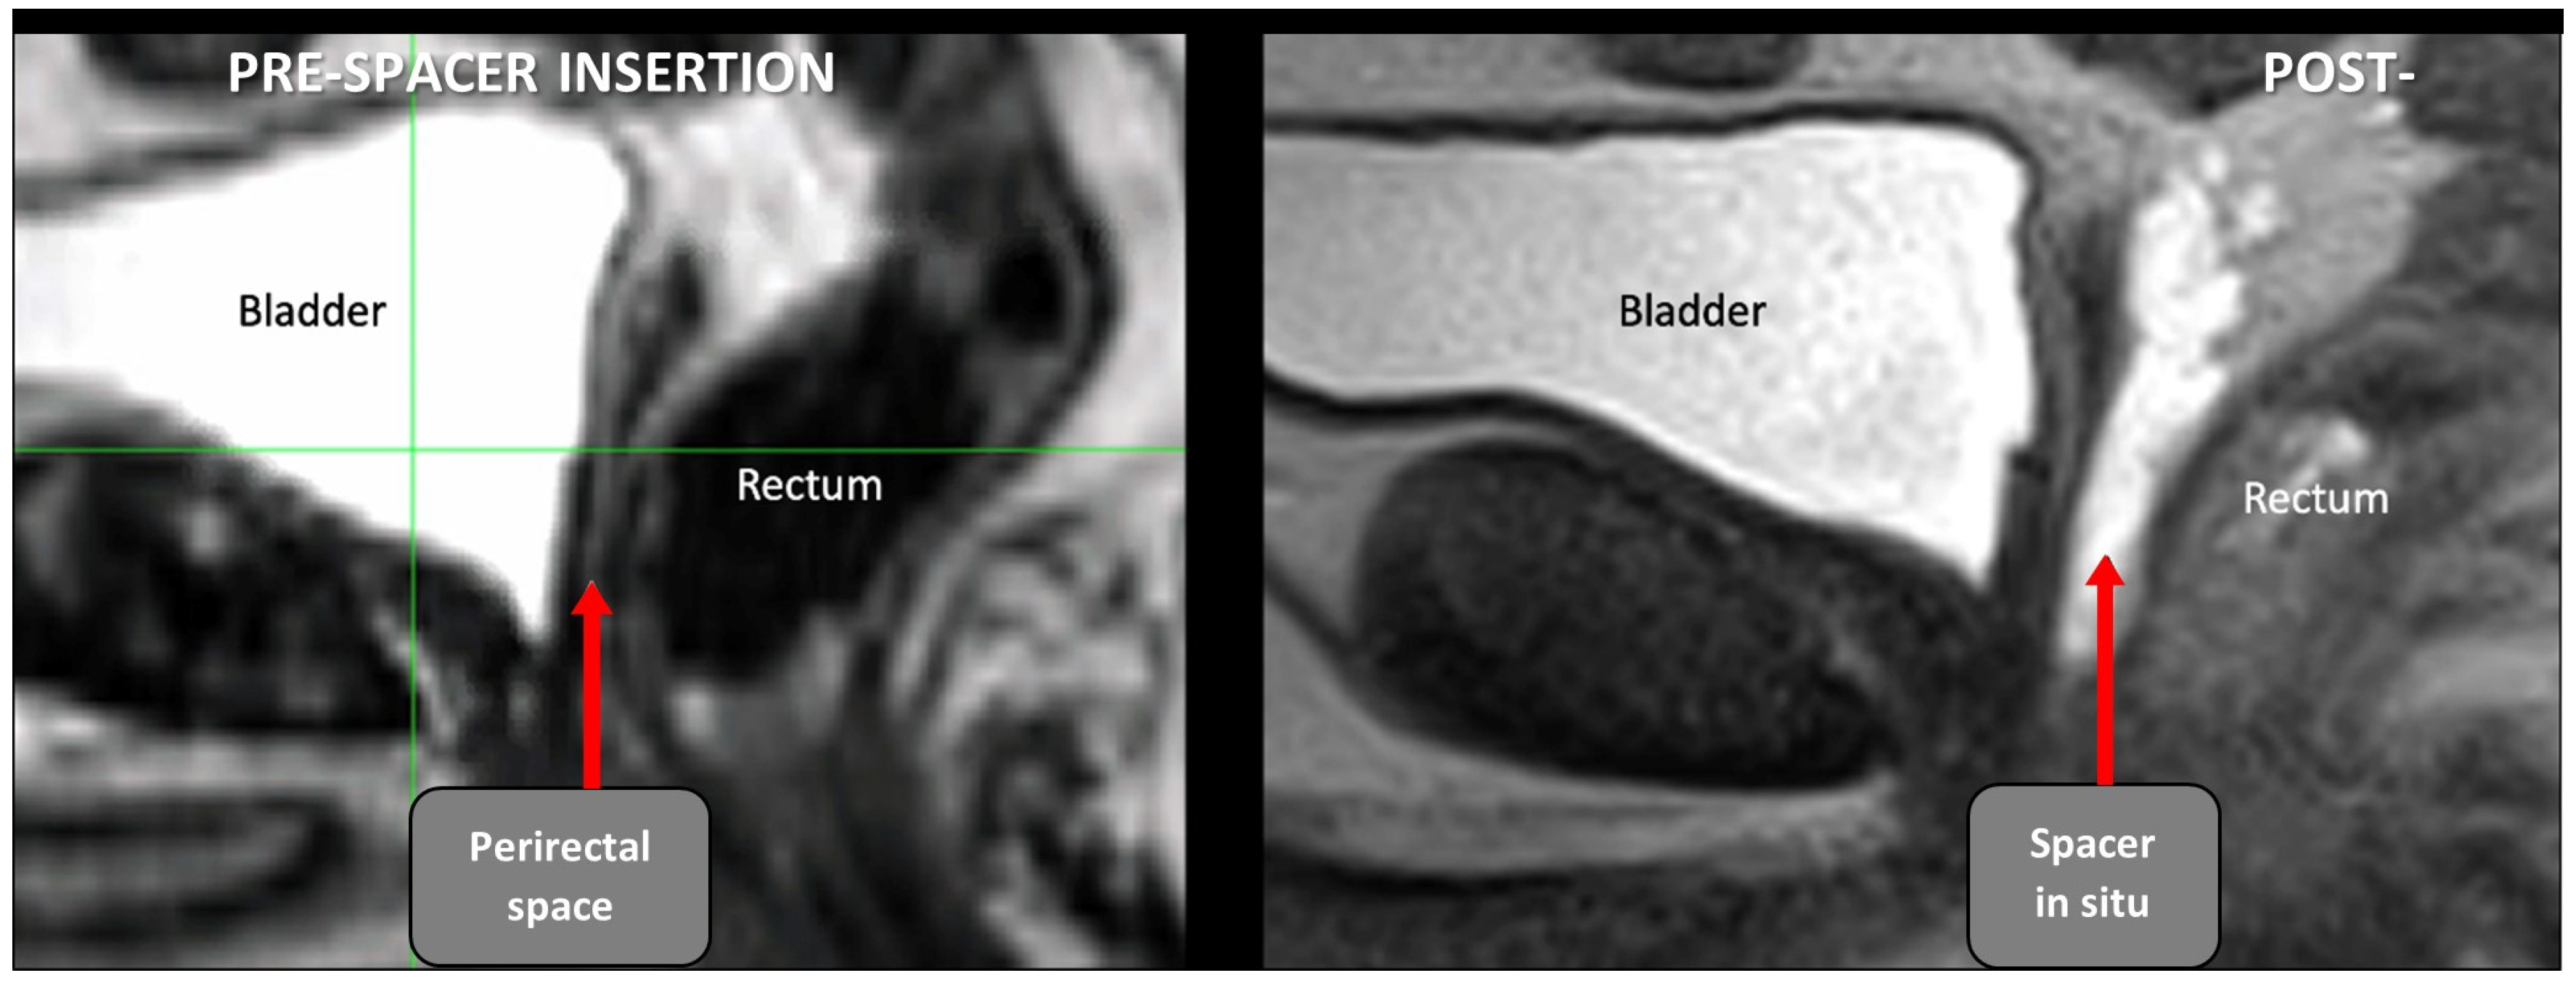

Patients underwent rectal spacing with either hyaluronic acid (Barrigel®, Palette Life Sciences, Santa Barbara, CA, USA) or hydrogel (SpaceOAR®, Boston Scientific, Massachusetts, Marlborough, MA, USA). The insertion technique is demonstrated in Figure 1. The rectal spacer was inserted into the perirectal fat posterior to the retained Denonvillier’s fascia between the bladder and anterior rectal wall using a transperineal approach under TRUS guidance. An indwelling urinary catheter was inserted to help delineate the vesico-urethral anastomosis (VUA). The perirectal fat was identified between the bladder and anterior rectum. An 18G spinal needle (Quincke Type Point® Spinal Needle, BD, Stockholm, Sweden) was inserted using a freehand technique targeting the midline of the prostate bed under sagittal TRUS guidance. Hydrodissection of the perirectal fat in the sagittal midline with 3 to 5 mL of sterile saline was attempted and, if successful, followed by insertion of 6 to 9 mL of hyaluronic acid (66% of cases) or hydrogel. After insertion, the vesico-rectal separation was calculated by measurement at the midline of spacer’s sagittal length. Pre- and post-spacer insertion images can be seen in Figure 2.

Figure 2.

Pre- and post-spacer insertion MRI images (sagittal) with hyaluronic acid in perirectal space extending just above pelvic floor.